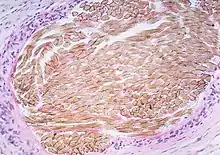

| Picture of a granuloma (without necrosis) as seen through a microscope on a glass slide: The tissue on the slide is stained with two standard dyes (hematoxylin: blue, eosin: pink) to make it visible. The granuloma in this picture was found in a lymph node of a patient with a Mycobacterium avium infection. | |